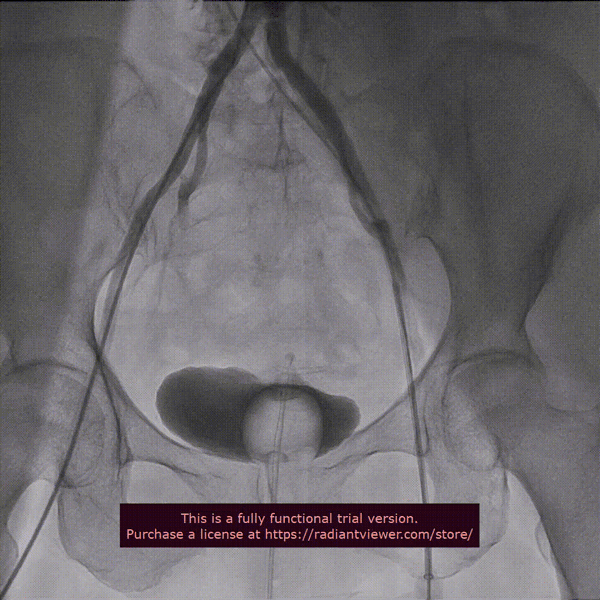

近日,中国医学科学院阜外医院潘湘斌教授团队,在多科室的通力配合下,凭借扎实的手术功底顺利完成一例经导管主动脉瓣和二尖瓣瓣中瓣置换术。

手术过程